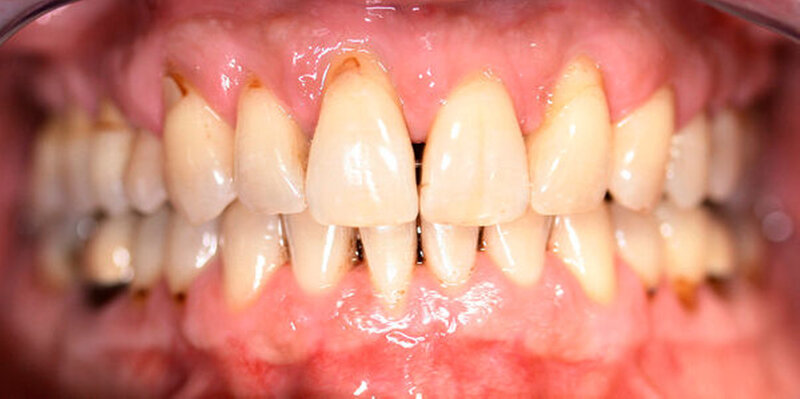

Röntgenologisch stellte sich im Orthopantomogramm der bereits intraoral ersichtliche horizontale und vertikale Knochenabbau mit Attachmentverlust an einzelnen Zähnen dar. Die Erhaltungswürdigkeit einzelner Zähne war aufgrund des starken Knochenverlustes beziehungsweise der Beeinträchtigung des Halteapparates als kritisch zu beurteilen.

Zudem wurde die Diagnose einer Parodontitis gestellt, die eine Rücküberweisung an den Hauszahnarzt erforderlich machte (Abbildung 2).